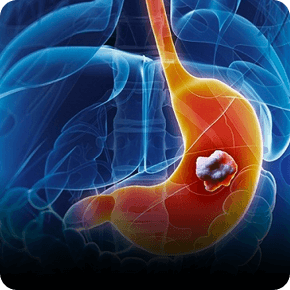

Mục tiêu tầm soát bệnh chính xác để trị hết bệnh, đem lại hạnh phúc cho người bệnh, Phòng khám đầu tư hệ thống máy móc tân tiến hiện nay, giúp bác sĩ đánh giá chính xác tổn thương và giúp sinh thiết chính xác vị trí tổn thương.

Với hệ thống máy nội soi hiện đại cùng công nghệ chẩn đoán hình ảnh tiên tiến, chúng tôi tập trung phát triển dịch vụ nội soi chuyên sâu nhằm phát hiện sớm và chính xác các bệnh lý tiêu hóa.